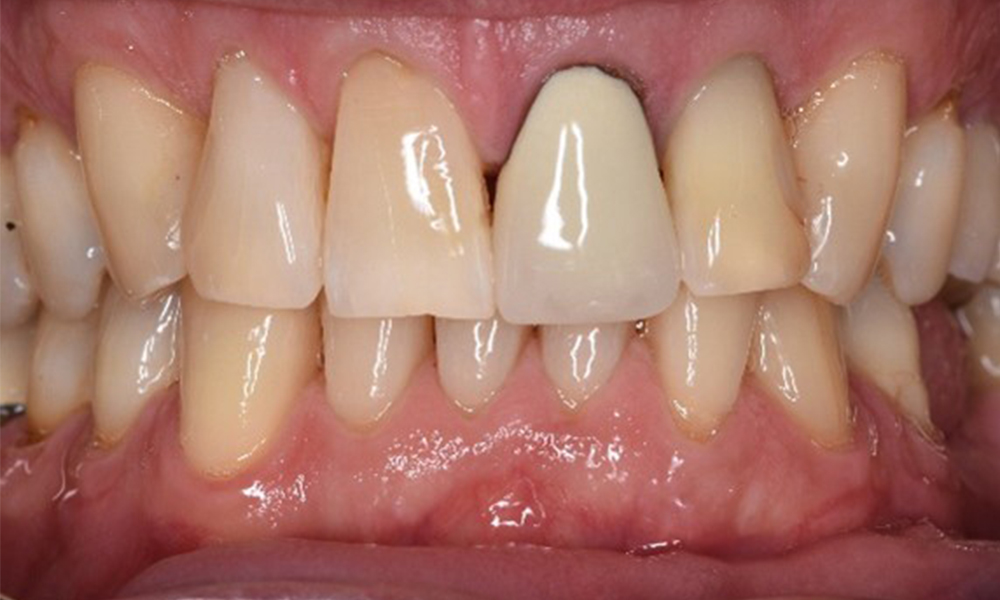

In the medical history, the 55-year-old patient states that he has no systemic disease and is not taking any medication. The patient’s lifestyle is similarly unremarkable. The patient has a few tooth restorations and two implants (2nd and 4th quadrants). On the basis of current findings, gingivitis is identified in an otherwise stable periodontal condition on the reduced periodontium (stage III, grade A).

Previous treatments: dental restorations (non-precious metal/ceramic blend), two implants (2nd, 4th quadrants)

The patient has no particular risk factors with specific dental implications. The key factor, therefore, is the requirement in terms of oral health. In this respect, good oral health is evident with stable, reduced periodontium. Should evidence of an increase in probe depth compared with the baseline, combined with diffuse bleeding, be found at a check-up appointment, diagnosis using X-ray imaging (dental X-ray) should be undertaken in order to identify peri-implant bone loss at an early stage and intervene accordingly.

Despite the stable condition, it is also important for this patient to be given motivation/instruction. Particular attention should be paid to correct care for implants. Here in particular, good at-home maintenance can have a significant impact on the long-term stability of oral and implant health.